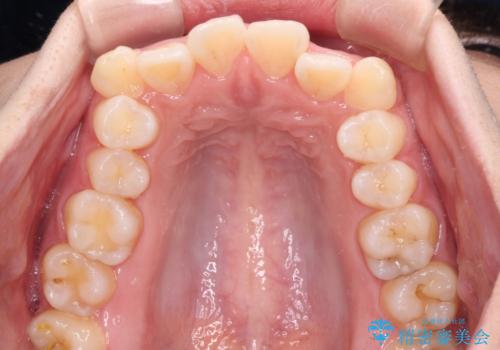

- 前歯の出っ歯と口元の閉じにくさを気にして来院された患者様です。

口元を積極的に引っ込めるために、上下左右の小臼歯4本を抜歯することとしました。